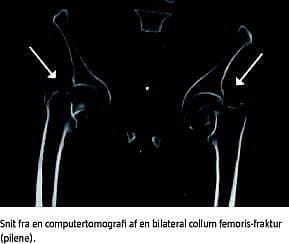

En 58-årig mand ankom om morgenen på skadestuen med smerter nedadtil i abdomen, over symfysen og i begge underekstremiteter. Patienten var frisk dagen forinden og kunne uden problemer følge sin genoptræningsplan efter en amputation et halvt år før. Patienten havde diabetes og komplikationer deraf i form af diabetisk retinopati, diabetisk nefropati med dialysekrævende nyreinsufficiens, diabetisk makroangiopati med bilateral crusamputation for hhv. 16 og et halvt år siden, desuden havde han mb. Crohn. Pga. komorbiditet og et diffust symptombillede blev der foretaget computertomografi af abdomen og hofter med opmærksomhed på tarm- eller underekstremitetsiskæmi. Herved fandt man en bilateral fraktur af collum femoris. Der havde ikke været nogen form for traumer. Patienten havde ikke tidligere haft lavenergibrud.